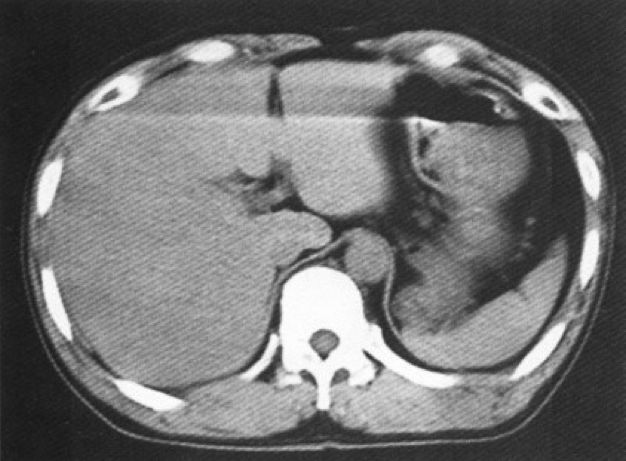

(超高分辨率成像)